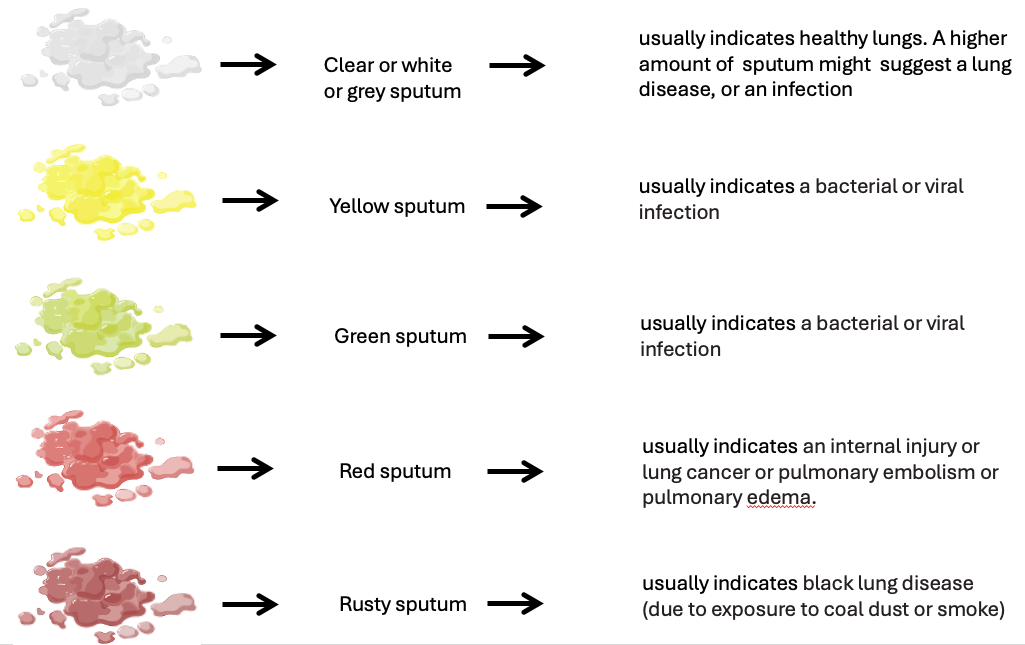

3 – Signs & Sympoms: sputum (yellow, green, red, rusty, thick tenacious), hemoptysis, breathing sounds and pace, eupnea, laboured, wheezing stridor, rales, rhonchi, absence, dyspnea, orthopnea, cyanosis, pleuritic pain, friction rub, clubbed fingers

hemoptysis – is a medical term for coughing up blood from airways or lungs. It is different from vomiting blood or bleeding from nose or mouth. Blood coughed up due to haemoptysis will likely be frothy and bright red. The symptoms include but not limited to fever, fatigue, chest pain, weight loss and shortness of breath.